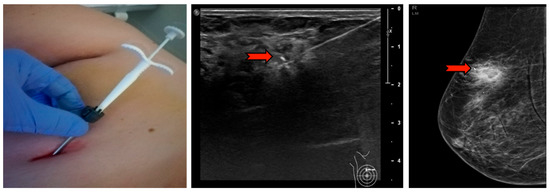

The ultrasound VABB Elite biopsy was performed using a sterile disposable 13G 2.6 mm probe, 13.6 cm in length and with a biopsy site 18.4 mm in width which, thanks to a cable-free and more compact handpiece, compares favorably with the simplicity and functionality of the CB (Figure 1). In Figure 2, we summarize the workflow of the VABB Elite procedure. The straightforward insertion of the needle into the breast is carried out only once, by means of a flat blade end and a double-lumen probe connected to a handpiece. This procedure does not necessitate the use of scalpels even in the presence of dense breasts or hard and fibrous specimens, thanks to the needle’s high capacity of penetration and manageability, which also allows good system control during the procedure and a 360° rotation within the biopsy area typical of the VABB.

Figure 1.

Vacuum-assisted breast biopsy (VABB) Elite ultrasound-guided biopsy handpiece, manageable and slightly larger than a core biopsy (CB) handpiece.

Figure 2.

Workflow of the VABB Elite procedure. The biopsy finding is initially identified on the ultrasound; 5–10 mL of lidocaine s.c. is then administered (perilesional subcutaneous); the biopsy needle is visualized by ultrasound (red arrow in the figure) until the sampling site is reached; the procedure is started with a 360° rotation at the pick-up, cutting and automatic suction of the whips in the collection container located at the base of the handpiece; at the end of the procedure it is possible to extract the needle and the handpiece, leaving in place a cannula for the insertion of a localization clip visible in ultrasound and mammography up to 6 months after the procedure.